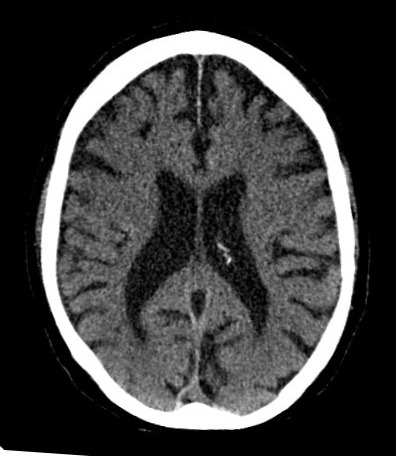

- Chest X-ray – can be used to image any problems or abnormality in lung pathology (e.g. pleural effusions etc).

- Computed Topography – can be used for an intensive and more detailed imaging of injuries and abnormalities in the anatomical pathology (e.g. detection of pulmonary emboli or airway tumor).